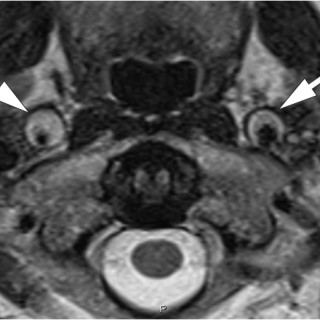

En mann i 70-årene ble henvist hematologisk poliklinikk grunnet redusert allmenntilstand og anemi. Blodprøver viste hemoglobin 9,7 g/dl (13,4–17,0), gjennomsnittlig cellevolum i de røde blodcellene (MCV) 115 fl (82–98), leukocytter 3,0 · 10 9/l (3,5–11,0), trombocytter 187 · 10 9/l (145–348), folat 7,2 nmol/l (> 8,0), kobalamin 693 pmol/l (175–700) og ferritin 831 µg/l (34–300). Tilstanden ble oppfattet som megaloblastisk anemi på grunn av folatmangel, og man startet med folatbehandling. Kontroll etter to måneder viste vedvarende anemi med hemoglobin 9,4 g/dl. Benmargsutstryk med May-Grünwald...